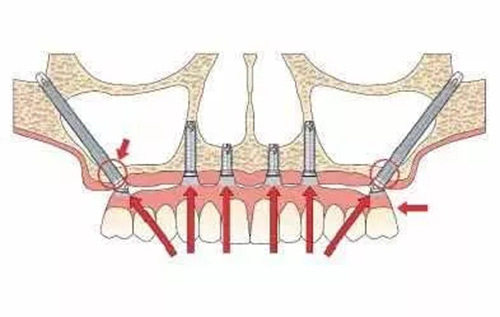

传统种植牙要求牙槽骨至少有8-10mm高度,但上颌骨重度萎缩患者(牙槽骨高度<5mm)根本达不到标准。穿颧种植直接绕过萎缩的牙槽骨,把3-5cm长的种植体植入颧骨(眼眶外下方骨质厚达15-20mm),相当于在“贫瘠土地”上找到了“肥沃新土壤”。

传统植骨需等待3-6个月愈合,穿颧种植无需植骨,全口无牙患者植入4-6颗穿颧骨植体后,当天就能改善基本咀嚼功能。临床数据显示,其5年成功概率达95.7%,与常规种植牙(97%)相近。

1.手术难度高,风险大

穿颧种植需穿透颧骨和翼突骨,这两个区域密布三叉神经分支、面神经和血管。若操作偏差1.5mm,就可能导致神经损伤,表现为面部麻木、肌肉运动障碍或持续性疼痛。经验不足的医生操作神经损伤率高达8%,而资历深医生可控制在1%以下。